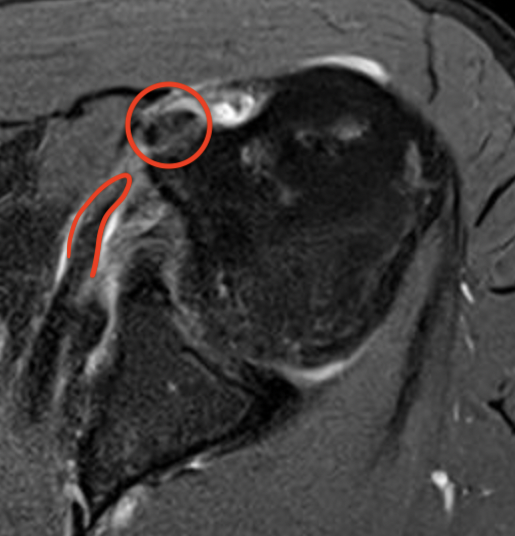

Full thickness retracted subscapularis tear with medial dislocation of long head of biceps tendon

Comma sign

- medially retracted subscapularis tear

- exposes the superior insertion of superior glenohumeral ligament / coracohumeral ligament

Full thickness retracted subscapularis tear with comma sign